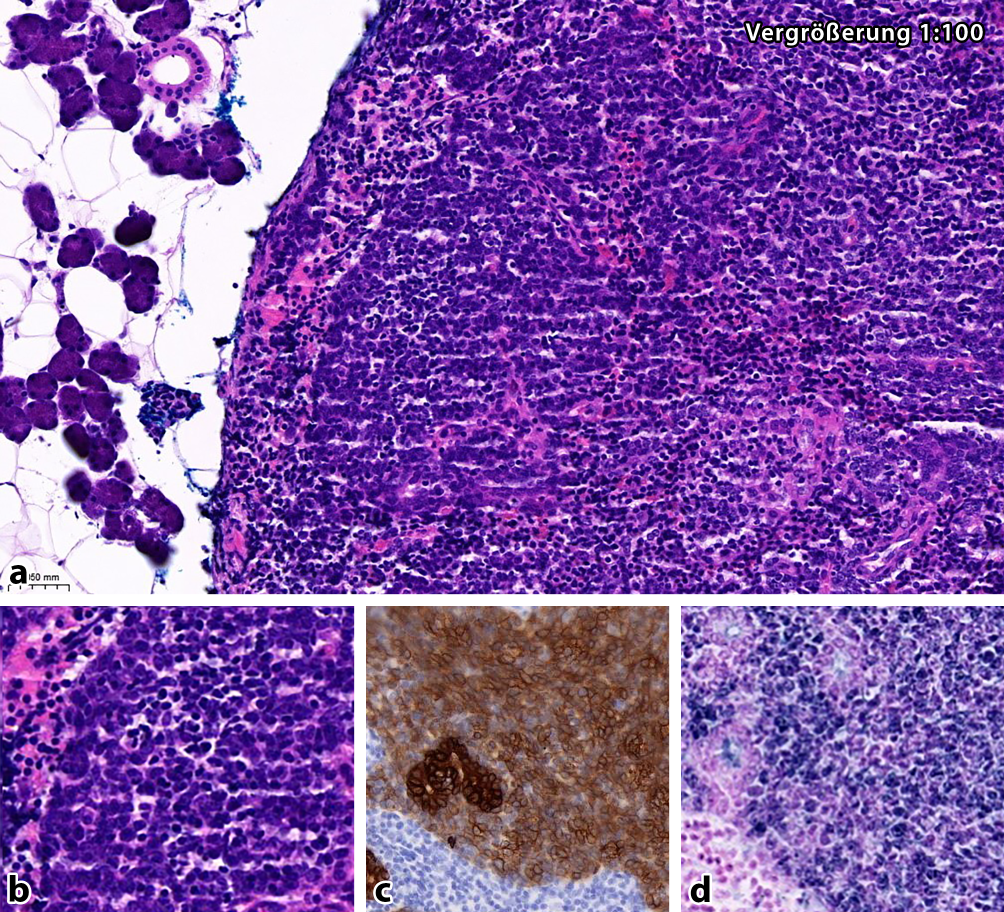

Histologisch kam eine synzytial gewachsene epitheliale Neoplasie mit ausgedehntem assoziierten lymphozytär dominierten Entzündungsinfiltrat zur Darstellung (ab). Immunhistochemisch zeigte sich eine positive Färbereaktion für Panzytokeratin (c), p40 und CK5/6 bei Negativität für p16 und positiven Signalen in einer EBER-in-situ-Hybridisierung (d). Bei unauffälliger Panendoskopie des übrigen HNO-Gebiets wurde die Diagnose eines EBV-assoziierten lymphoepithelialen Karzinoms der Parotis gestellt. In einigen ethnischen Gruppen (insbesondere bei der Inuitpopulation sowie der südchinesischen, japanischen, nordafrikanischen und mongolischen Population) machen lymphoepitheliale Karzinome 3,6–92 % der malignen Speicheldrüsentumoren aus, wohingegen sie in nichtendemischen Regionen nur 0,3–0,7 % der Speicheldrüsenmalignome repräsentieren [1]. Die Läsion wurde zweizeitig operiert. Im Präparat der Restparotidektomie zeigten sich keine weiteren Anteile des lymphoepithelialen Karzinoms